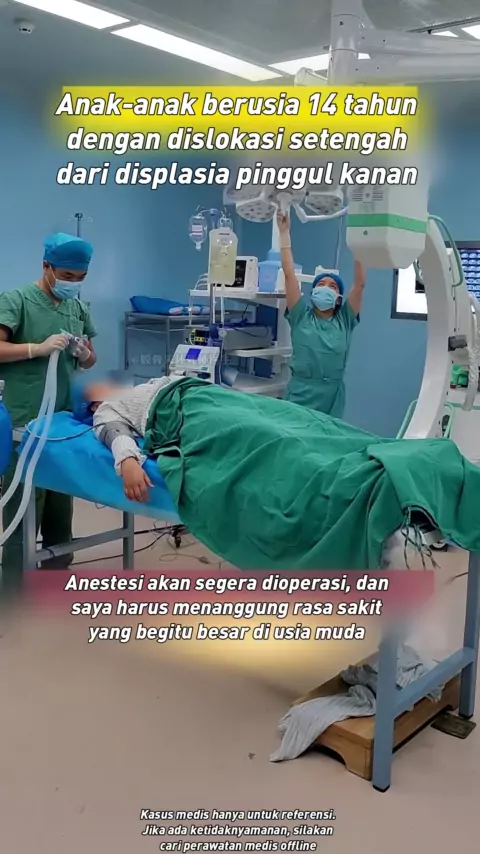

Anak berusia 14 tahun dengan displasia pinggul kanan dan dislokasi separuh. Anestesi akan segera dilakukan. Gadis kecil itu bijaksana dan pendiam saat menunggu anestesi. Dia sangat pendiam dan tidak menangis atau membuat masalah. Dia sangat tertekan. Dia harus menanggung rasa sakit yang begitu besar di usia muda! # kongenital hip displasia # femoralis nekrosis # femoralis nekrosis # Hal yang tidak Anda ketahui di ruang operasi